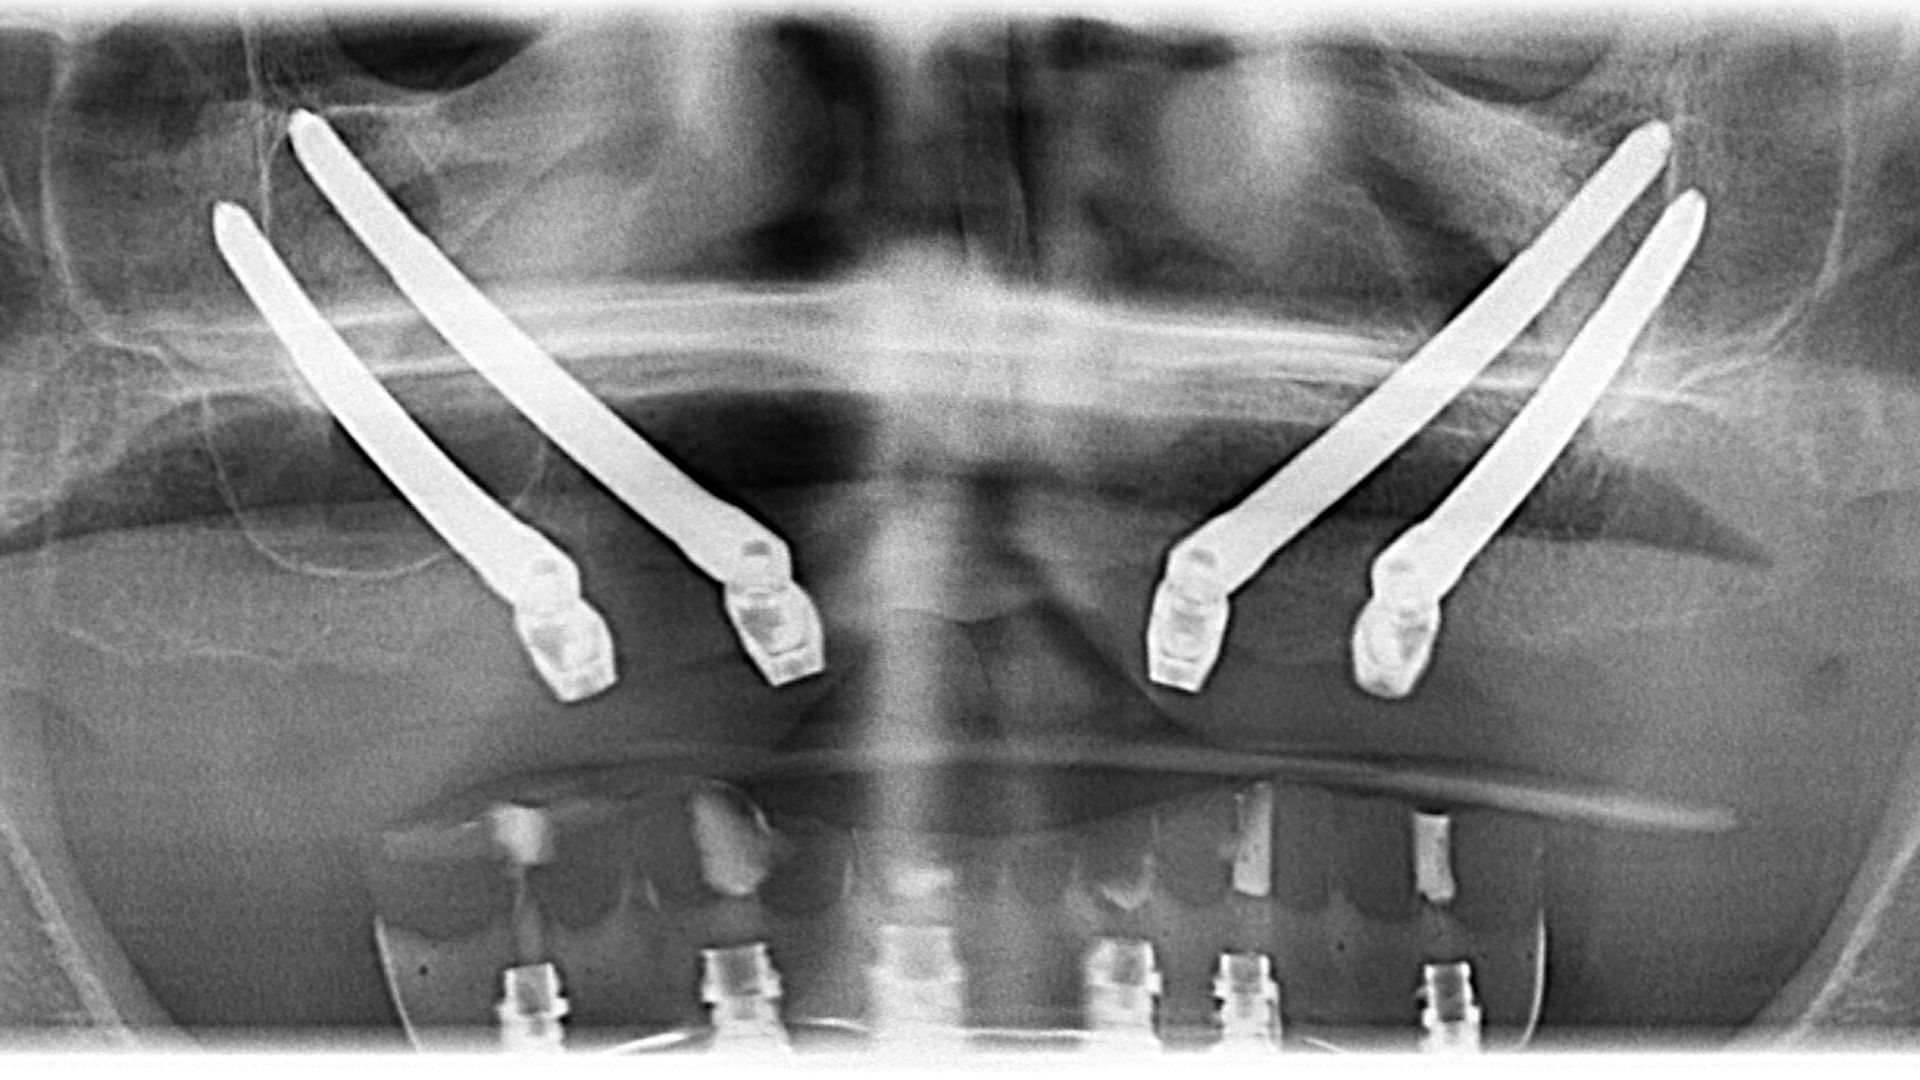

If for years you have suffered from missing jaw teeth and have been rejected by dentists multiple times due to the same old diagnosis - lack of bone mass for the insertion of classic implants - today, there is a solution for you! With the help of zygomatic implants, we can offer you a fixed solution on 4 implants. The difference between a zygomatic all-on-4 and a classic all-on-4 lies in the length of the implants, the direction of insertion, and the position of the implants. While classic implants are inserted parallel to the maxillary sinus and in the frontal bone mass of the jaw, zygomatic implants are inserted into the zygomatic bone and sometimes through the maxillary sinus. Zygomatic implants are made of titanium and are 30-60 mm long, depending on the patient's clinical case. The operation is performed under local anesthesia, if necessary in conscious sedation, supervised by an anesthesiologist, and is performed by a maxillofacial surgeon assisted by an oral surgeon. If for years you have suffered from total tooth loss and have suffered from a removable prosthesis, this implant protocol can be your last resort.

The first step is a specialist visit that includes a CT scan, a thorough clinical examination, and a consultation with a maxillofacial surgeon. During the visit, the surgeon can assess the condition of the jaw bone and plan the appropriate protocol for zygomatic implant placement. There are two solutions: Hybrid (includes 2 zygomatic implants and 2 to 4 classic implants inserted in the front of the jaw) and Quad (includes 4 zygomatic implants). After careful analysis, the surgeon decides which implant placement protocol can be done for the patient and prepares a quote for the procedure. If the patient accepts the quote, all necessary appointments are made to perform the implant placement surgery and the production of the temporary fixed prosthesis. The definitive fixed prosthesis is produced after 3-5 months from the surgical implant placement procedure.